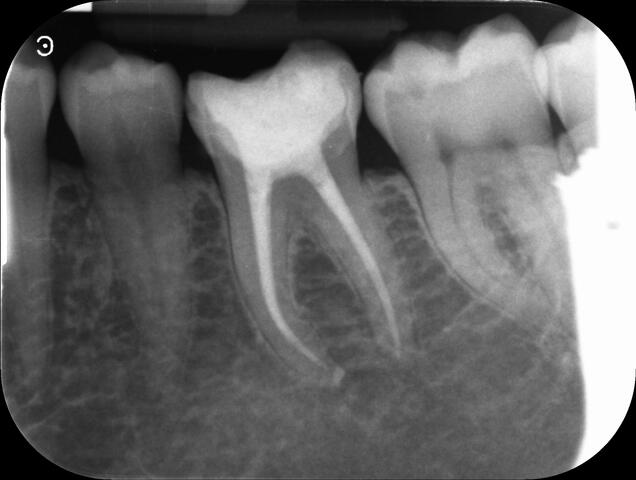

I am pleased to take endodontic referrals. Curved canals >30 degrees and potentially greater than 50 degrees can be negotiated. Sclerosed canals accessed. Post spaces prepared and the patient returned to you ready to restore.In most cases existing crowns, bridges and veneers can be retained with the endodontic access aesthetically restored after the full canal network has been treated.In the first instance I would prefer a radiograph and a brief list of patient expectations and a tooth history.

I really enjoy undertaking root canal treatments - rising to the challenge and helping people out of dental pain for the long term.I was privileged to be asked to speak at the 2016 BDA Conference, where I have a lecture about providing quality endodontic outcomes to patients, working as a generalist. Avoiding problems and pitfalls and maximising efficiency. One of the main matters that he covered was understanding that what is seen on plane radiography is utterly misleading and should not be the criteria by which a generalist continues treatment once it has been started.

At the 2016 BDA Conference, Thomas spoke about providing quality endodontic outcomes to patients, working as a generalist. Avoiding problems and pitfalls and maximising efficiency. One of the main matters that he covered was understanding that what is seen on plane radiography is utterly misleading and should not be the criteria by which a generalist continues treatment once it has been

started.